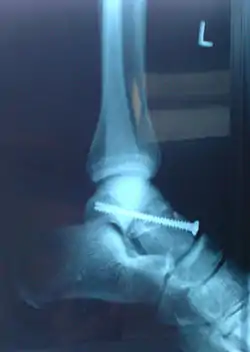

Fractură cominutivă a colului talusului tratată prin osteosinteză internă (fixarea fragmentelor fracturii cu șurub)

- Osteosinteza corticală constă în fixarea cu șuruburi care trec prin ambele corticale ale fragmentelor osoase.